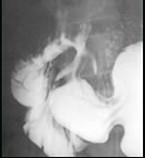

问题 男,32岁,中上腹空腹痛,进食后缓解,剑突下轻度压痛,钡餐检查如图,最可能的诊断是 ( )

选项 A、十二指肠节段性肠炎 B、十二指肠结核 C、十二指肠憩室 D、十二指肠球部溃疡 E、十二指肠癌

答案 D